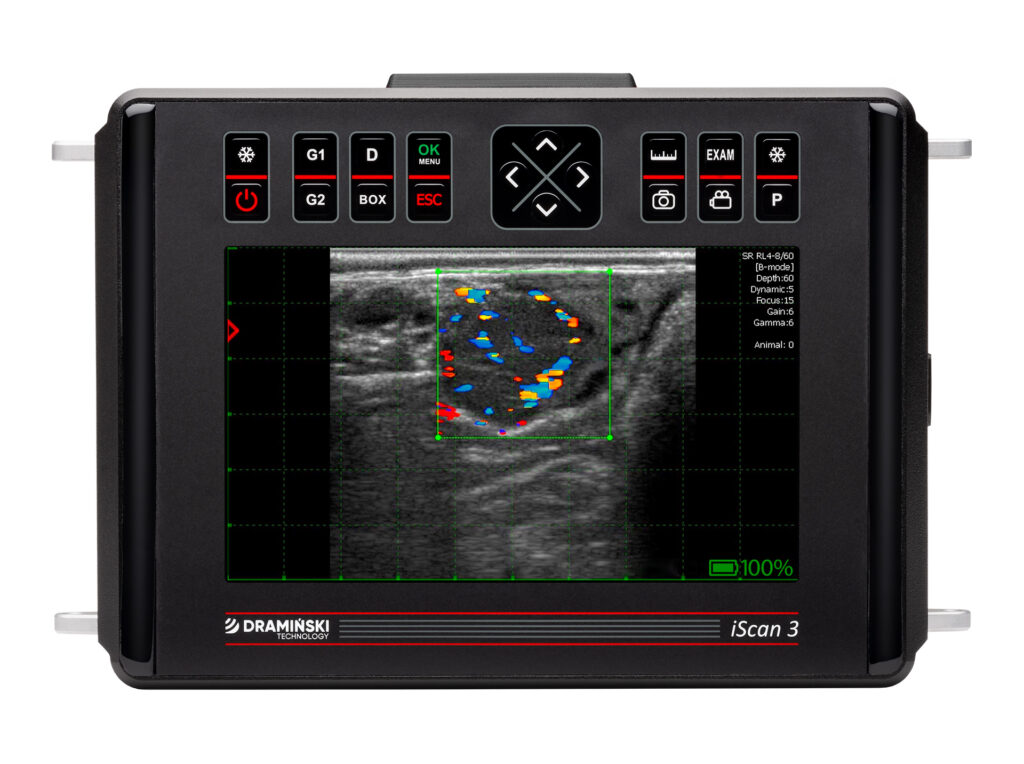

El examen ecográfico Doppler puede ser útil en el diagnóstico y la evaluación del pronóstico. La presencia de flujo sanguíneo dentro de la lesión aumenta la probabilidad de éxito de la terapia antibiótica sistémica, ya que el fármaco es capaz de llegar al lugar de la infección.